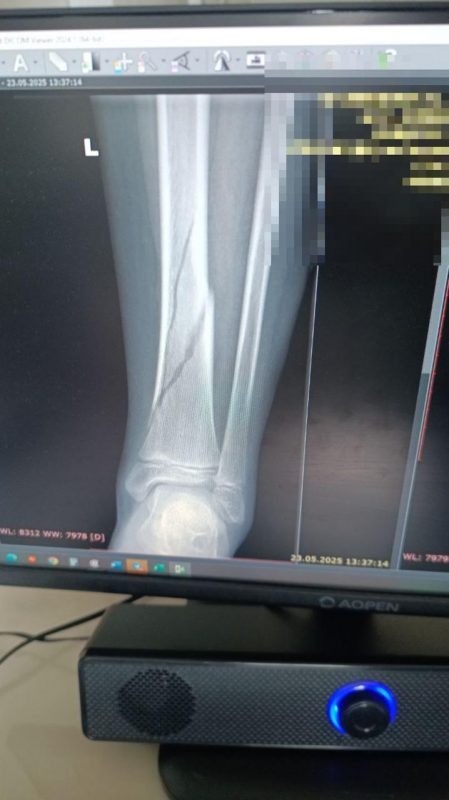

После того, как девочка выбралась из раздевалки, она, естественно, бросилась к своим обидчицам. Но хулиганки подставили ей подножку и Александра упала. Как отмечает Мария, мама пострадавшей, была не только подножка, но и удар ногой. В итоге у девочки диагностировал серьезный перелом берцовой кости. Сейчас пострадавшей приходится передвигаться на инвалидной каталке, так как такие переломы болезненны и долго срастаются. Мама Александры в тот же день написала заявление в полицию.